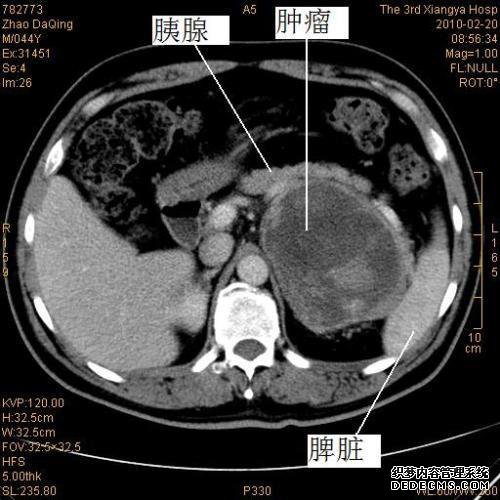

病情描述发病时间,主要症状,症状改变等):患者为65岁,EE显示胰腺颈部回声区略低,大小约为17。

9毫米* 14。

高血糖测试后发现2mm,进行MRI,CT扫描并显示胰腺颈部被占用

同时,对血样进行分析并正常。

CA199为23。

03,CA15-3为11。

5,CA-12514CA72-41。